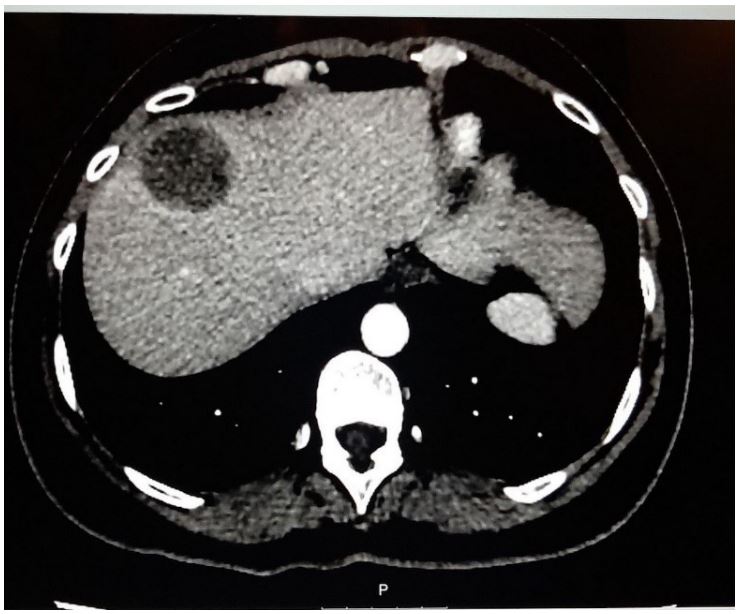

Initially, 4 cm right-sided breast mass was identified on ultrasound (Figure 1). From there, a core needle biopsy was performed, which demonstrated a fibroadenoma. However, the histology from the ensuing lumpectomy demonstrated the presence of a malignant PT. After several courses of radiotherapy, the discovery of the right-sided axillary lymph node necessitated PET-CT, which showed high intake of FDG (Figure 2). The corresponding core needle biopsy confirmed that it contained metastasized PT. After performing bilateral mastectomy with right axillary lymph node dissection, the histology proved that the breasts were clear, but that 1/16 lymph nodes contained PT. Significantly, the occurrence of an additional axillary mass a couple months later prompted an abdominal and chest CT. This demonstrated metastases in the axillary, mediastinal, and retroperitoneal lymph nodes, with liver metastasis (Figures 3 and 4). No further biopsies were performed, and follow-up abdominal and chest CT demonstrated that the metastases had increased in size (Figures 5 and 6).

Figure 3: Chest CT demonstrating pathologic axillary and mediastinal lymph nodes.

Figure 5: CT demonstrating enlargement of axillary and mediastinal lymph nodes.